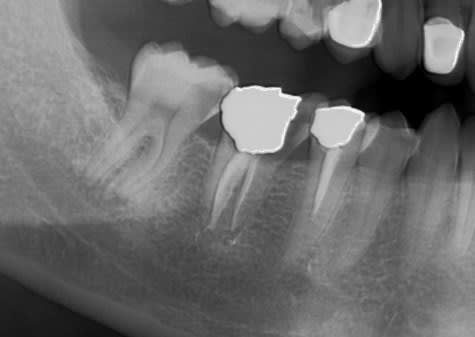

Pour réaliser un bridge qui tient la route et ne se descelle pas tous les 4 matin, il est parfois nécessaire de créer des artifices de rétention sur les moignons ou les IC, lorsque la hauteur coronaire est faible...

Lorsque la hauteur coronaire trop faible ne permet pas d'obtenir à la fois, un espace prothétique suffisant pour réaliser une prothèse esthétique, et une rétention convenable, je réalise un bridge Richmond.

On va encore me traiter de chieur mais t'es a 2 mm de l'apex de la 47 en distal, bonne chance pour démonter un truc comme ça pour faire le RTE si problème...

Je ne pense pas être à 2 mm de l'apex radiologique. Par contre je suis à l'apex détecté par le localisateur. Je reprendrais d'autres rétro sous différents angle pour voir...

Tu coupes le bridge au niveau de l'inter, et tu te retrouves avec :

- une endocouronne sur 47 avec à peine 1 mm de hauteur coronaire en distal ;

- une couronne Richmond sur 45

La couronne provisoire sur la 47 n'aurait pas tenu 1 semaine avec du ciment provisoire classique, malgré la cavité interne. J'ai dû la scellé avec du provitemp (ciment provisoire renforcé à la résine) pour être sûr ;-)

Le truc, c'est qu'avec un bridge comme ça, si ça se descelle au niveau du pilier postérieur au bout de 2 ou 3 ans, tu es quand même bien embêté... D'où le recherche d'une meilleur rétention.